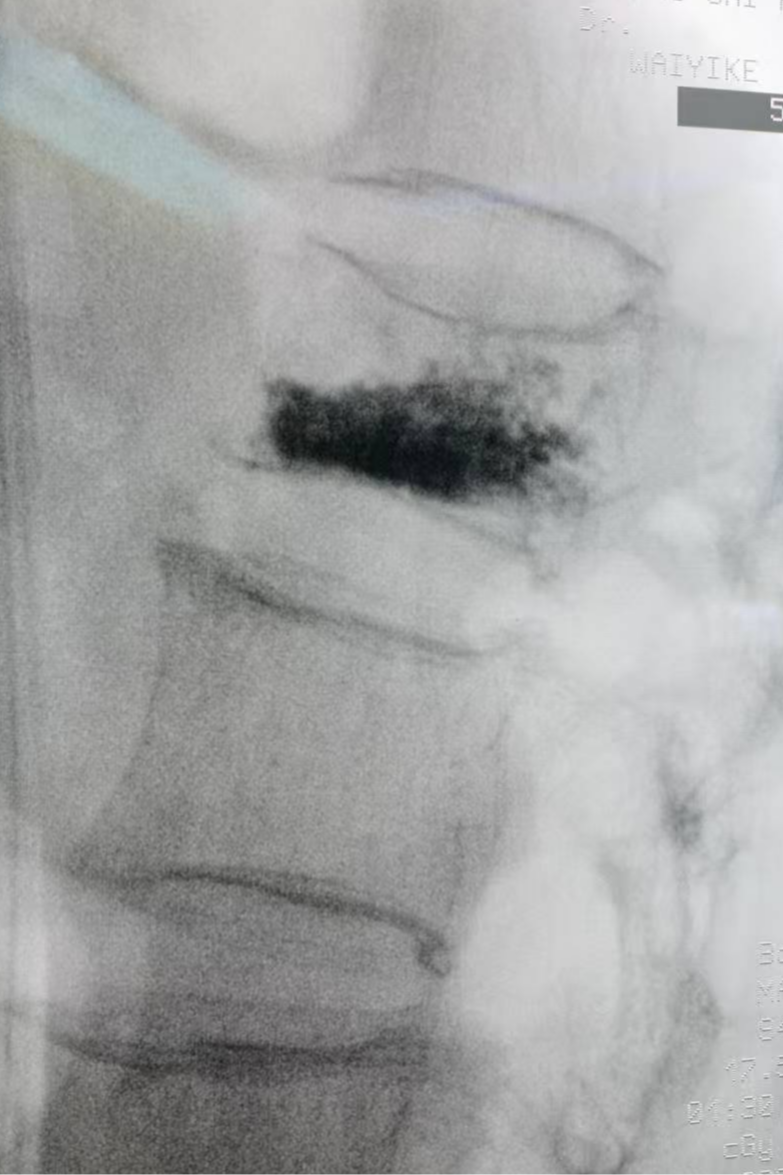

第1腰椎骨折术后正位X线片、侧位X线片,椎体黑色部分为手术注入的骨水泥